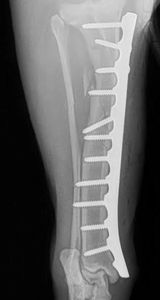

This patient was a large adult dog who was stuck by a car. This caused a complete short oblique fracture of his tibia. Due to his size, the nature of the fracture and his energy level traditional methods of stabilization (splinting etc) had risk of failure or inadequate healing.

During surgery, the fracture was reduced and a 3.5mm broad LCDCP was placed to stablize the fracture. By the time he arrived for his suture removal he was comfortable and walking almost normally. View the video below to watch him walk two weeks after surgery.